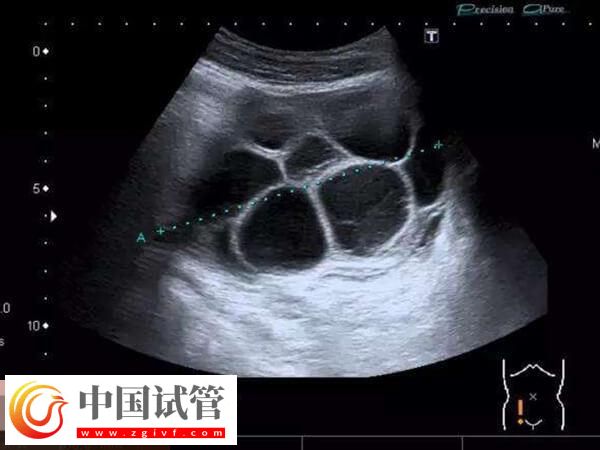

2、卵巢过度刺激综合征

取卵后卵巢过度刺激综合征,这也是导致女性在移植术后腹水的重要原因,这种病症主要是有对于促排卵药物的剂量使用把握不准,或者女性的体质较为敏感,对于卵巢刺激过度,从而诱发卵巢刺激综合征,进而导致腹水。